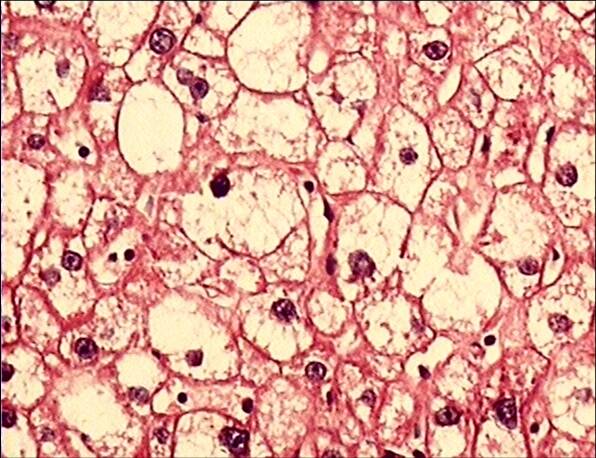

肝细胞水肿:肝细胞明显肿大,胞浆稀疏甚至透明, 又称水样变性或气球样

胞浆疏松化,进一步发展肝细胞胀大如球形,胞浆几乎透明,称为气球样变

肝细胞水变性(气球样变) 弥漫性肝细胞体积增大,胞质淡染清亮

细胞核被推挤至周围(a);箭头所示为气球样变肝细胞(b);箭头所示为围绕